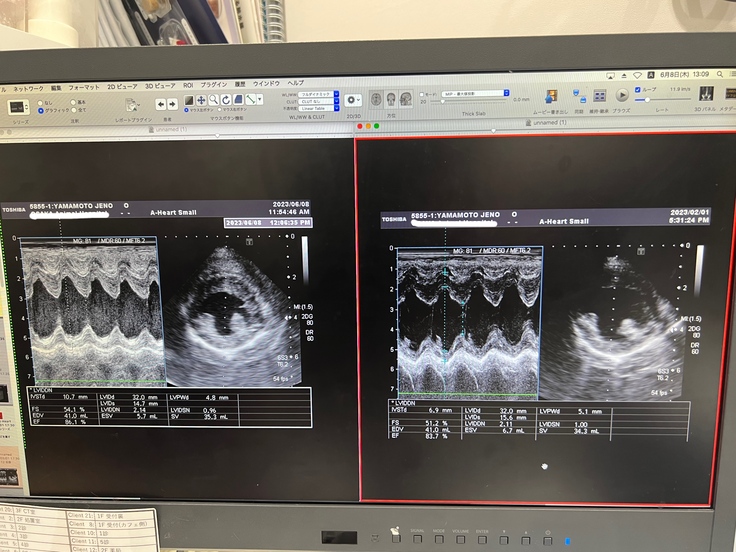

※心臓のエコー写真